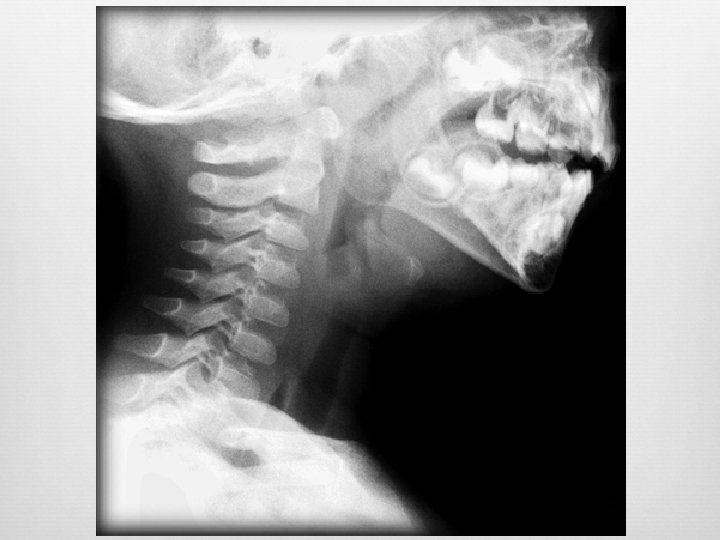

Epiglottitis Enlarged epiglottis Loss of valecular airspace Thickened aryepiglotic folds Distended hypopharynx Straightening of the cervical spine Sensitivity (38 -88%) Specificity (78%) Croup and epiglottitis: a radiologic study. AU Stankiewicz JA; Bowes AK SO Laryngoscope 1985 Oct; 95(10): 1159 -60. Epiglottitis and croup. AU Sobol SE; Zapata S SO Otolaryngol Clin North Am. 2008 Jun; 41(3): 551 -66, ix. Adult epiglottitis: the Toronto Hospital experience. AU Solomon P; Weisbrod M; Irish JC; Gullane PJ SO J Otolaryngol. 1998 Dec; 27(6): 332 -6.

Adult Epiglottitis Radiographic Criteria Epiglottic height-to-width ratio >0. 6 Epiglottic to C 4 vertebral body width ratio >0. 33 Aryepiglottic fold to C 3 vertebral body width ratio >0. 35 Prevertebral soft-tissue to C 4 vertebral body width ratio >0. 25 Hypopharyngeal airway to C 4 vertebral body width ratio >1. 5